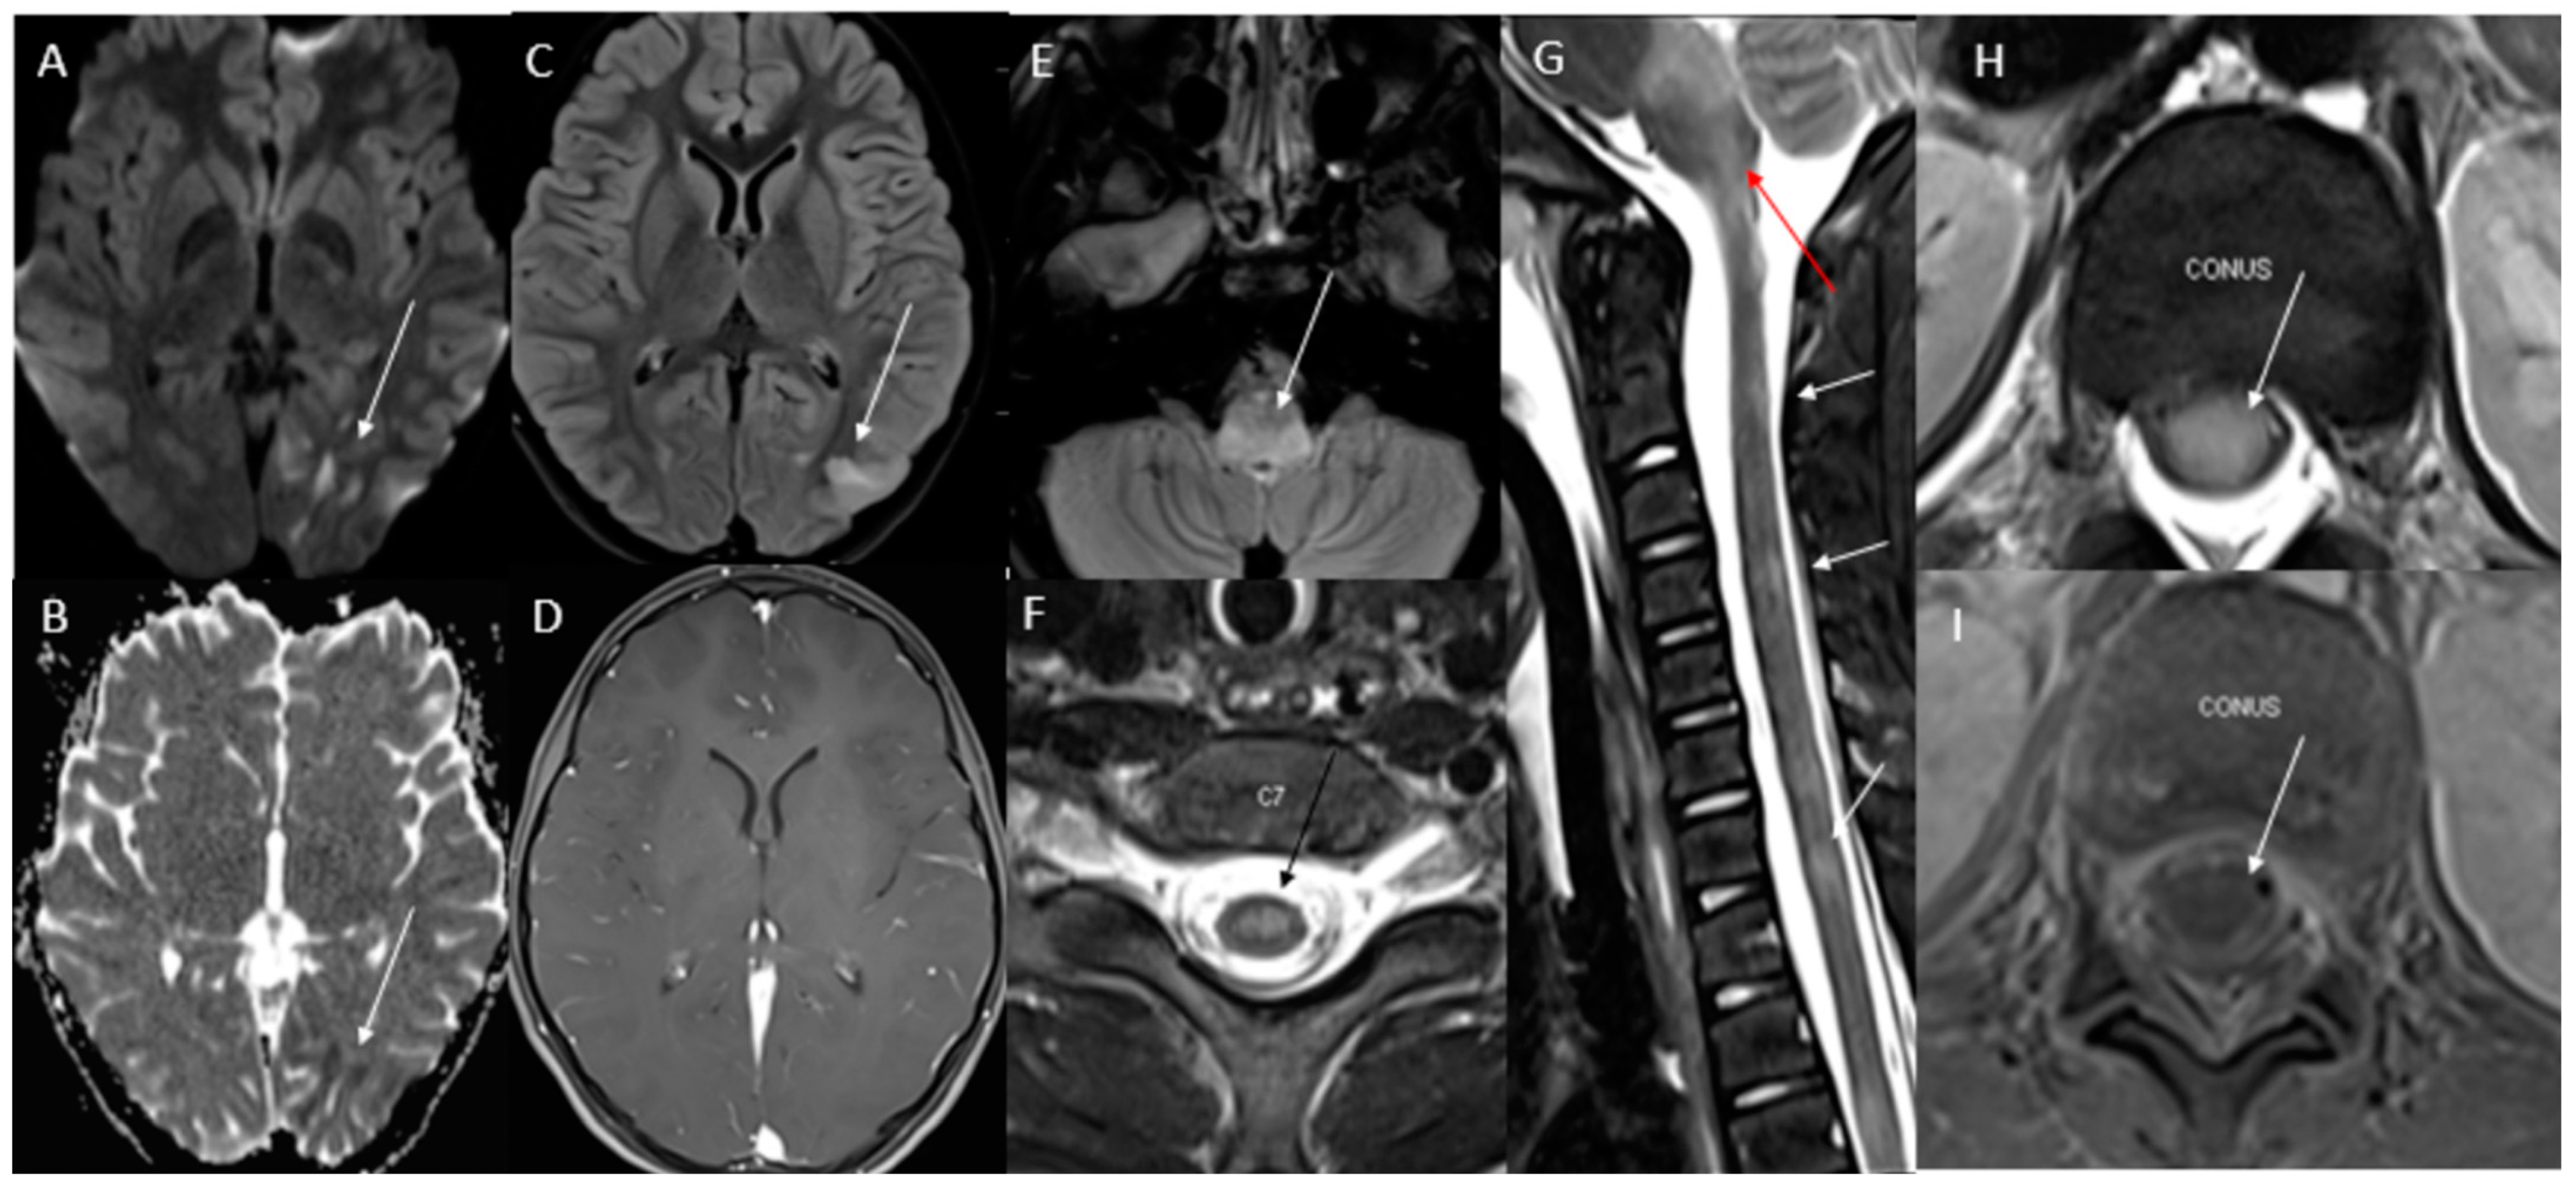

6.2. Neuroimaging Findings and Pathways Affected Leading to Urinary Retention